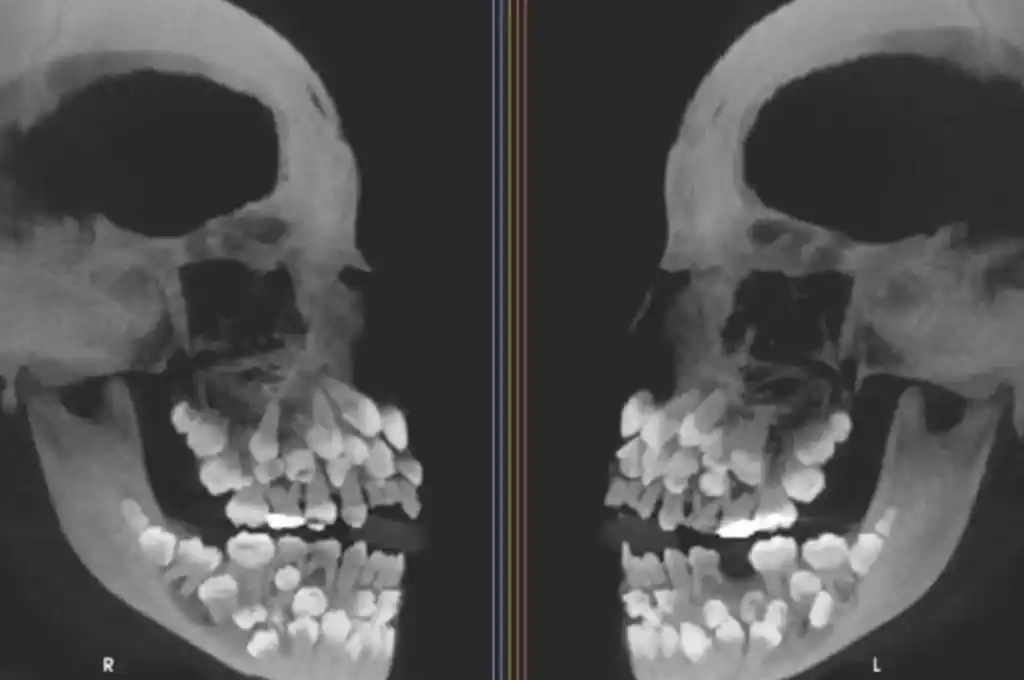

Una de las imágenes que exhibe el informe sobre este inusual caso es una tomografía computada de haz cónico (CBCT) tomada desde los dos laterales del rostro de la pequeña. Allí se ve, en blanco sobre negro, la exagerada cantidad de piezas dentales con las que cuenta esta paciente, que asemejan a un ramillete de dientes distribuidos tanto en el maxilar superior como en la mandíbula.

Las tomografías computadas permitieron hacer el conteo de las 81 piezas dentarias que posee una niña de 11 años.